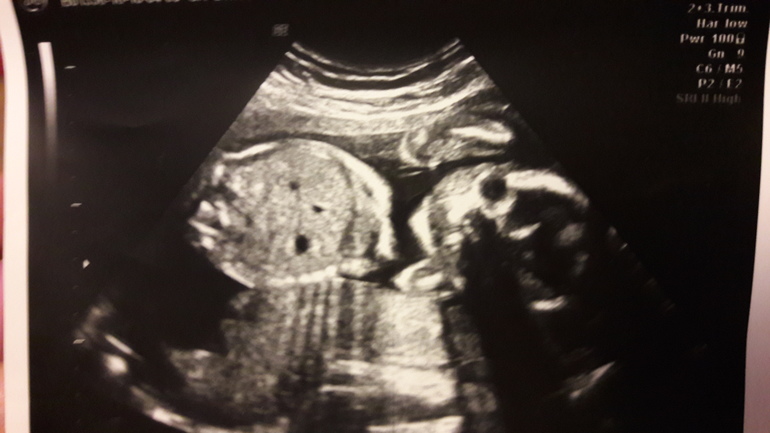

22+...или

Полных 5 месяцев и начало 6ого.

Ну вроде лёд тронулся, а то так долго... Ну мне так жежется... Была на скрининге раньше не много.,потому что живот тянул. Тонус малый по з/с матки ну и гиперэхогенная взвесь ещё есть. А так всё хорошо! 152кд в мин, 436 грамм... Девочка моя. Видео, фото, я.. Всё под ножницами...

Моя девчонка!!!! Пока лидирует Олеся ....